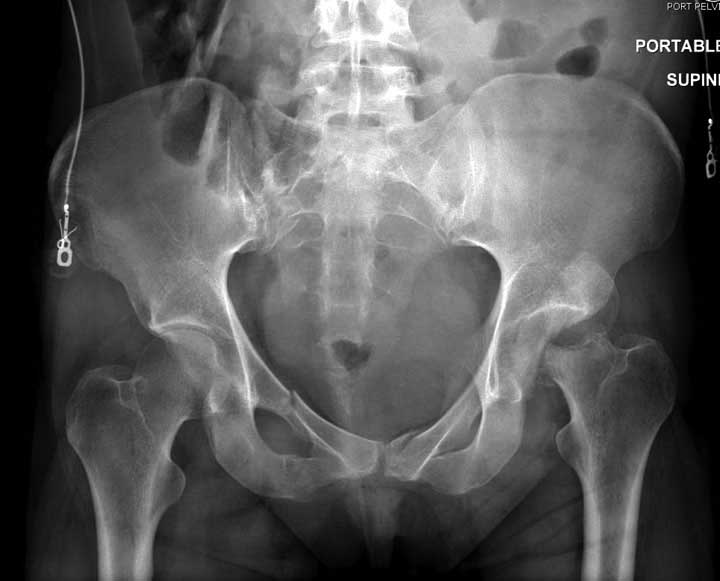

В диагноз еще необходимо внести закрытую (?) ротационно-нестабильную травму таза с переломами лонных седалищных костей, боковой массы крестца справа.

1. Тазовые щипцы, при невозможности (неимении) АВФ на передний отдел таза с попыткой ручной дистракции левого бедра.

Перелом позвоночника и боковую компрессию таза отнесли к стабильным переломам и не стали форсировать события до лучших времен...

После спадения отека на стопе произведена фиксация тарана. Кстати, коллеги пересмотрели первоначальную консультацию по позвоночнику и на двух уровнях провели фиксацию. Из-за длительного постельного режима без нагрузки таз не стали оперировать...